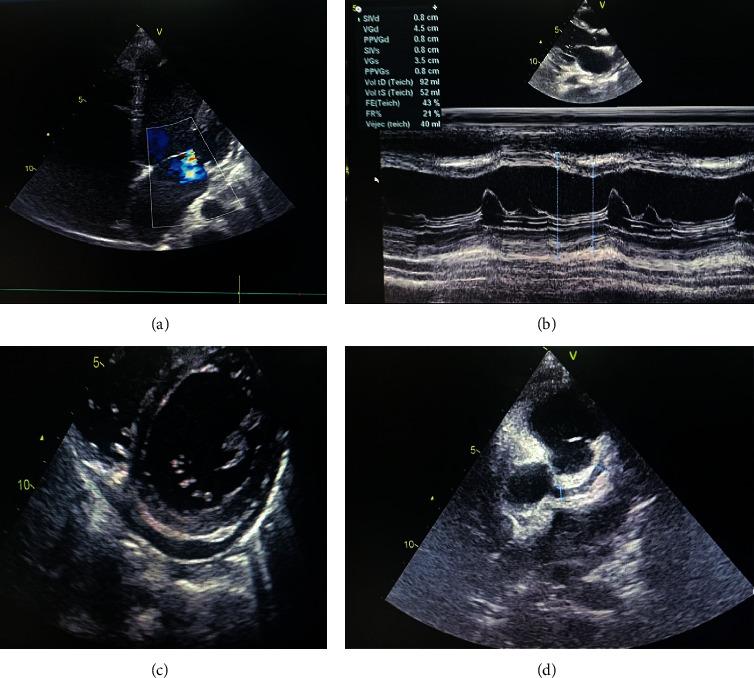

Kawasaki disease (KD) is a vasculitis mostly seen in children aged less than 5 years. It can involve different organs and tissues. Its diagnosis is based on the clinical criteria of the American Heart Association (AHA). We report a case of a Moroccan adolescent with an atypical presentation of KD initially treated as typhoid fever. Gastrointestinal, renal, and pulmonary signs were the main clinical findings that made the diagnosis of KD challenging and delayed. The consequence was a severe cardiac damage with myocarditis and coronary artery dilation. KD is uncommon in adolescents, and it is important to recognize the atypical forms and the different presentations of KD in order to prevent the delay of diagnosis and treatment, and hence the cardiac complications.

川崎病(KD)是一种主要见于5岁以下儿童的血管炎。它可累及不同的器官和组织。其诊断基于美国心脏协会(AHA)的临床标准。我们报告一例摩洛哥青少年川崎病非典型表现的病例,该病例最初被误诊为伤寒热。胃肠道、肾脏和肺部症状是主要临床发现,这使得川崎病的诊断具有挑战性并导致诊断延迟。结果是出现严重的心脏损害,伴有心肌炎和冠状动脉扩张。川崎病在青少年中并不常见,认识到川崎病的非典型形式和不同表现对于防止诊断和治疗延迟以及由此导致的心脏并发症很重要。